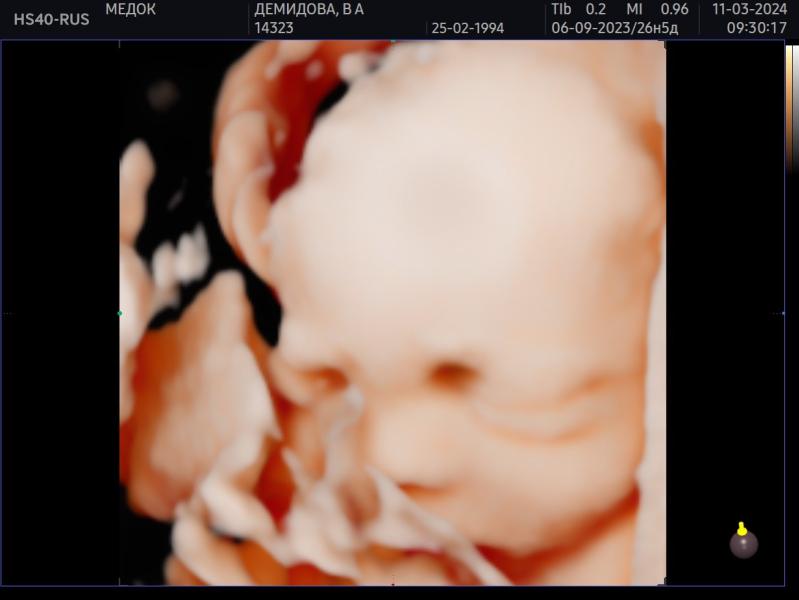

Была сегодня на 3д/4д узи в своей клинике, где веду беременность - Медок Марфино. Узист Лункина ЕГ (вдруг кто тоже туда планирует идти).

Проходила у нее два скрининга, будет у нее же третий, и вот сегодня промежуточное узи.

Срок 27.5 по 1 скринингу, так и опережаем месячные на неделю.

Сын весит около 1163 г. Ваши детки сколько весили на таком сроке?

Врач говорит что хороший вес для этого срока.

В целом все в порядке, лоханки так и остались слегка расширены, но врач сказала это не страшно. ...